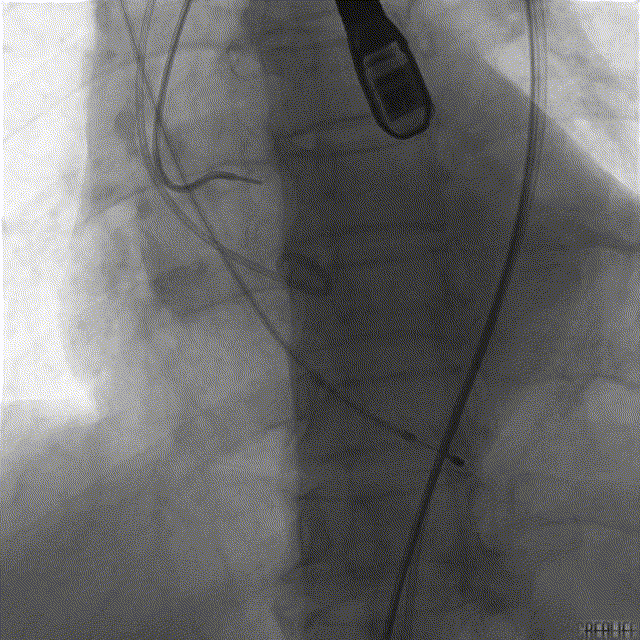

两次球扩,第一次向主动脉内滑脱,第二次球囊扩张真诚,未见明显腰征,按术前评估选择AV29号瓣膜。

造影下第一次释放,定位不理想,回收后预备重新释放。

精准再定位,释放于预定位置,瓣膜工作状态良好,造影示微量瓣周漏。